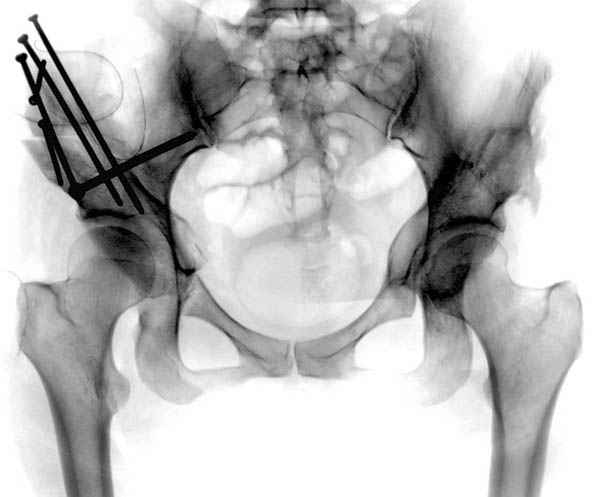

Рентгенограмма здесь дает достаточно информации для осознания бесперспективности консервативного лечения - более чем очевидный дефицит покрытия головки, coxa valga и т.д. Никакое консервативное лечение, и "протезы синовиальной жидкости" в том числе, эту проблему не решит. Конечно, если пациента обезболить и поставить на костыли на несколько недель, это улучшит его самочувствие на какое-то время. А если думать о долгосрочной перспективе - надо планировать хирургическое лечение.

Иван, да тут угол Виберга 0 градусов. Какое уж консервативное лечение. Кистозная перестройка - типичный компенсаторный (?) процесс при такой дисплазии.

Картина типичной эволюции дисплазии сустава "кистовидная перестройка", на фоне неправильного взаймоотношения сустава "да тут угол Виберга 0 градусов" на вершине наибольшей нагрузки в вертлужной впадине образовался участок разрежения, "киста", в последующем через этот участок образуется перелом - стадия фрагментация дисплазии.

Для установки диагноза достаточно информации, на рентгенограмме передний и задний край ацетабулум образовали перекрест, "цифру восемь", указывающий на небольшую ретроверсию, а суставная щель одинаковой ширины на всем протяжении, что доказывает, что с покрытием хряща проблем нет. Головка бедра покрыта всего наполовину, это явное нарушения взаимоотношений.